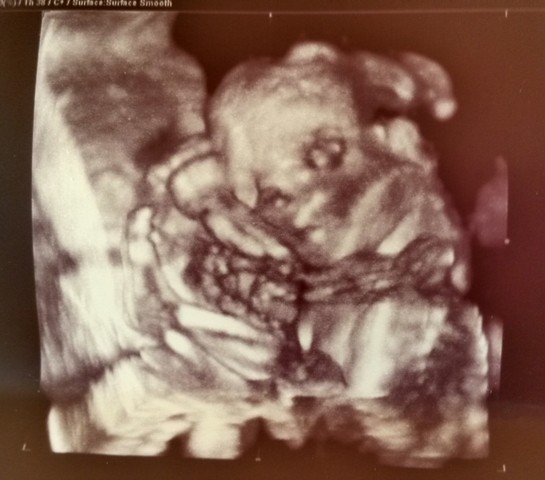

wspaniale, gratulace!!!wreszcie dotarłam do domu ... wizyta nam się opóźniła bo był poślizg i zamiast o 9 weszliśmy o 10 ... no ale wszystko jest w jak najlepszem porządeczkunarządy ok, no i wreszcie dowiedzieliśmy się płeć

Gin nawet zgodził się na nagranie na płytkę całego badania usg - i mamy filmik 11 min 30 sek

na 100% Synek![]()

Zobacz załącznik 708216